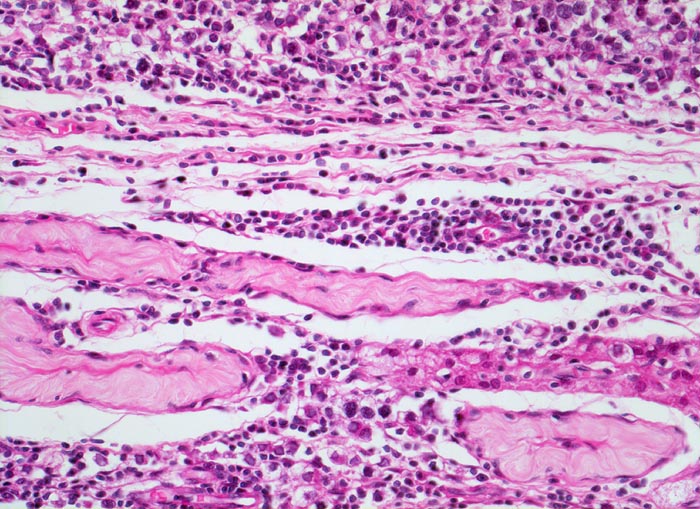

Seminom des Hodens

Aufnahme aus dem Tumorrandbereich. Zwischen den vollständig atrophen zellfreien Hodentubuli findet sich ein mononukleäres Entzündungsinfiltrat. Die Entzündungszellen maskieren die deutlich grösseren Tumorzellen.

Makroskopisch aus mehreren Knoten bestehender weisser Tumor von 2cm Durchmesser.

Der Patient suchte den Arzt wegen einer schmerzlosen Hodenvergrösserung auf.